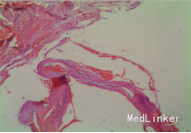

随访:行尿流率测定最大尿流率正常范围,排尿曲线较术前好转,彩超测定无残余尿,病理学检查示:送检双侧组织为纤维脂肪组织,有广泛出血。